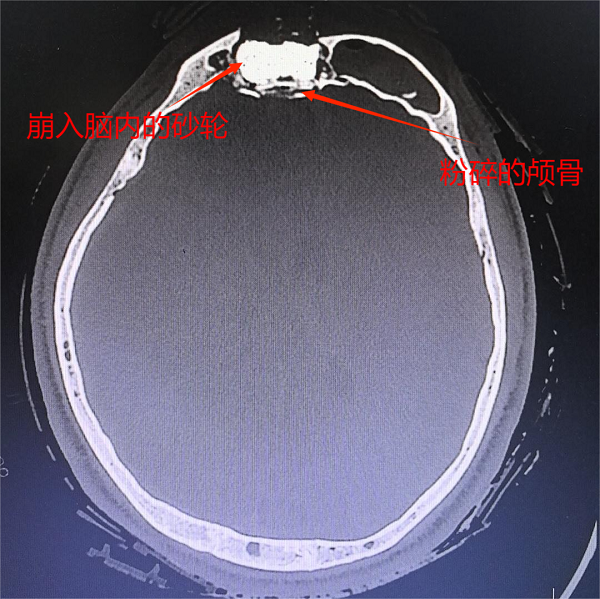

<b>金秋生命接力:多学科协作成功救治颅脑重伤少年</b>

金秋生命接力:多学科协作成功救治颅脑重伤少年